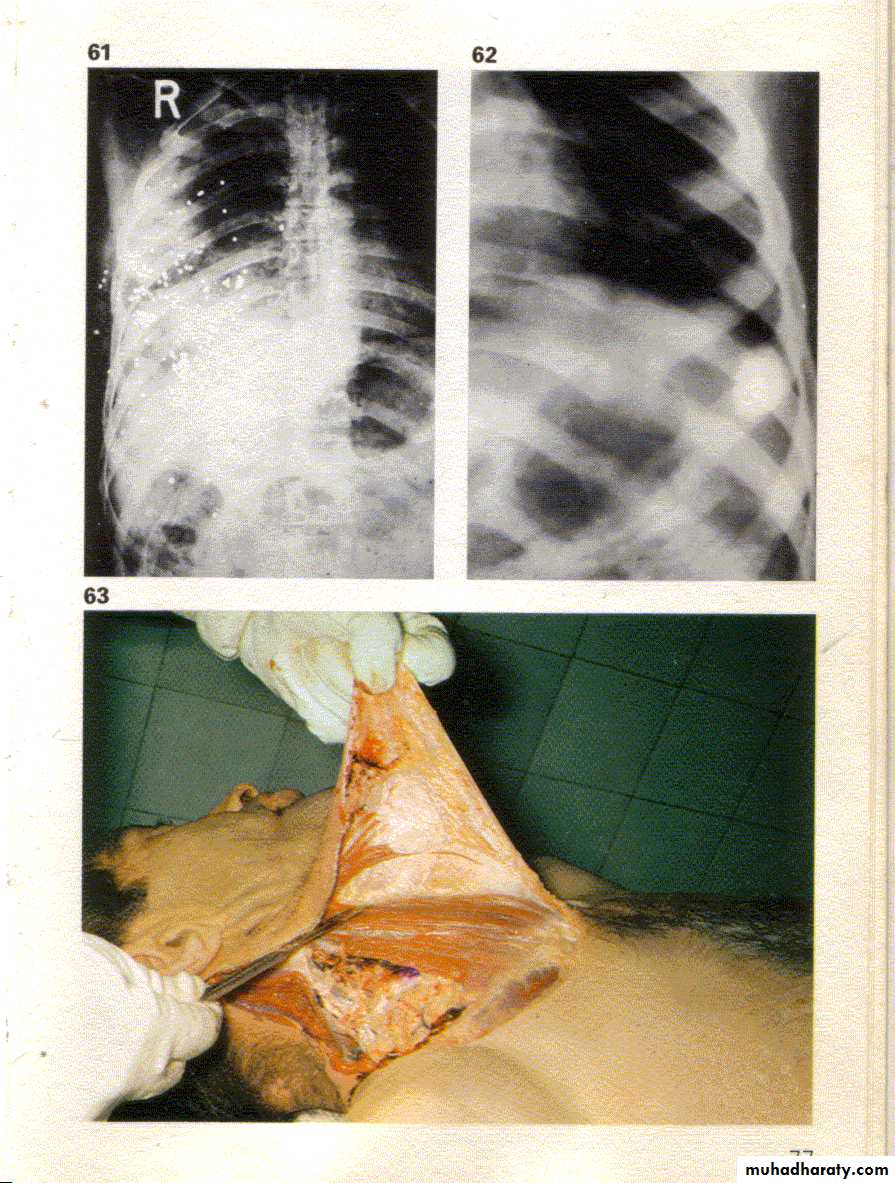

تصوير شعاعي للرئتين .

حيث يلاحظ وجود كرات معدنية متعددة صغيرة الحجم تسمى بالخرادق انتشرت في الرئة اليمنى مما يدل على أن السلاح الناري المستخدم في الحادث هو أملس السبطانة .3- مسافة الأطلاق مابين ( قدم – ياردة ) .